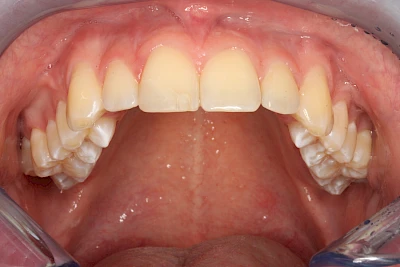

Verfärbungen an Zähnen können außen aufgelagert oder im Zahn eingelagert sein.

Von außen (exogen) eher dunkel gefärbt und meist mehrere Zähne betroffen:

- Genußmittel (Tee, Kaffee, Rauchen)

- Medikamente (z. B. Eisen)